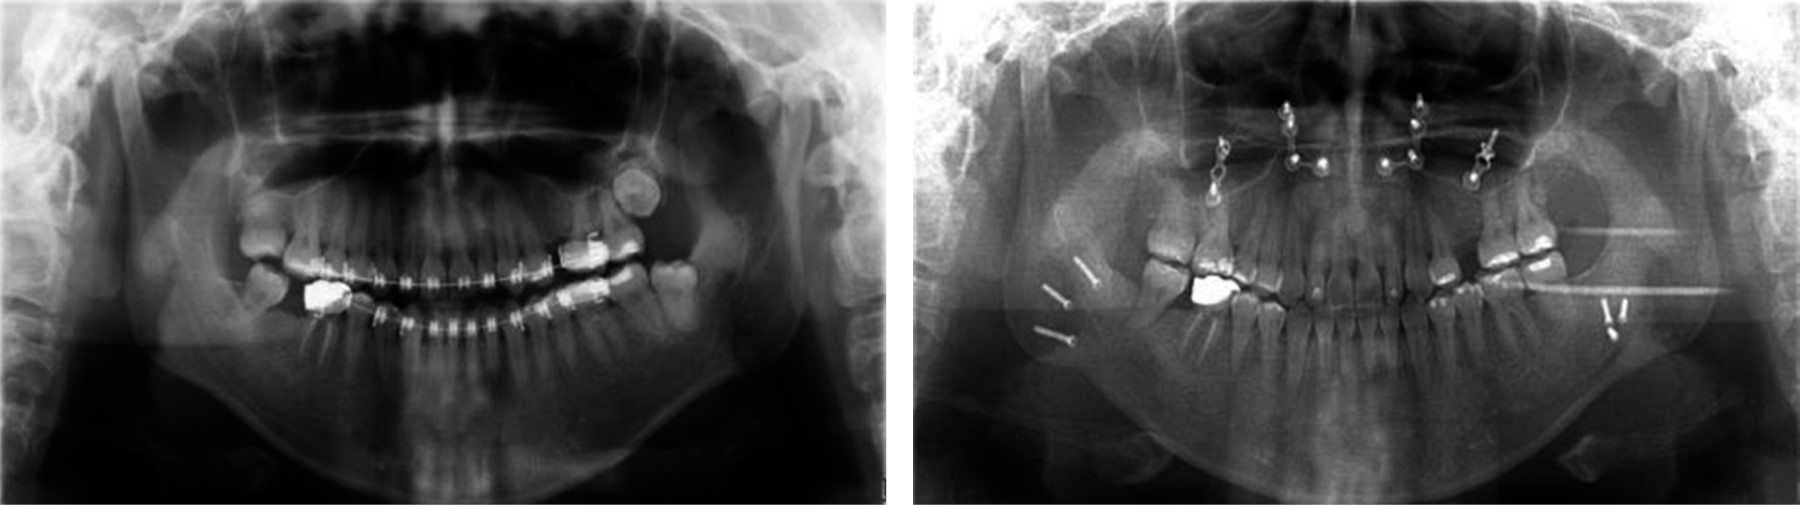

After the extraction of the third molars, we proceeded to the placement of fixed appliance Roth self-ligating slot 0.022" to begin phase I, starting with NiTi 0.014" archwires in both arches to begin with the alignment and leveling (Figure 6).

The treatment continued in the first phase, aligning and leveling, using 0.016" NiTi round archwires, and then begin to express torsional movements with 0.016" × 0.022" NiTi rectangular archwires, and 0.017" × 0.025" and 0.019" × 0.025" NiTi, then the same calibers were used but with a different alloy (stainless steel) (Figure 7).

Figure 6

Figure 7